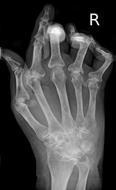

Normal hand RA - Damaged finger joints RA - Fused finger joint

Normal hand bones RA - Damaged hand bones RA - Damaged hand

https://commons.wikimedia.org/wiki/File:RheumatoideArthritisAP.jpg

Description   Typisches Röntgenbild einer

Rheumatoiden Arthritis.

https://commons.wikimedia.org/wiki/File:Rheumatoide_Arthritis_der_Hand_65W_-_CR_ap_-_001.jpg

Description      Deutsch: Rheumatoide Arthritis der Hand. Zusätzlich Fingerfrakturen.